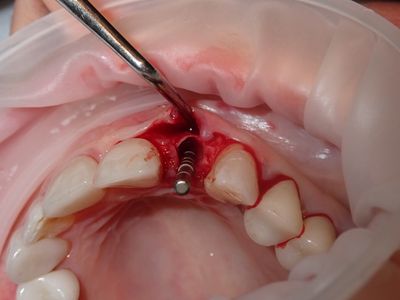

Atraumatic exo, loss of labial plate mid root about 2-3mm, CEJ and apical bone intact, region of thinner Labial-palatal bone, flapped site. osteotomy underprepared, implant placed with excellent stability. Buccal and socket grafted with 90/10 mix of mineralized cortical/xenograft followed by collagen membrane outside of socket on buccal, implant loaded with temporary crown out of centric and protrusive occlusion